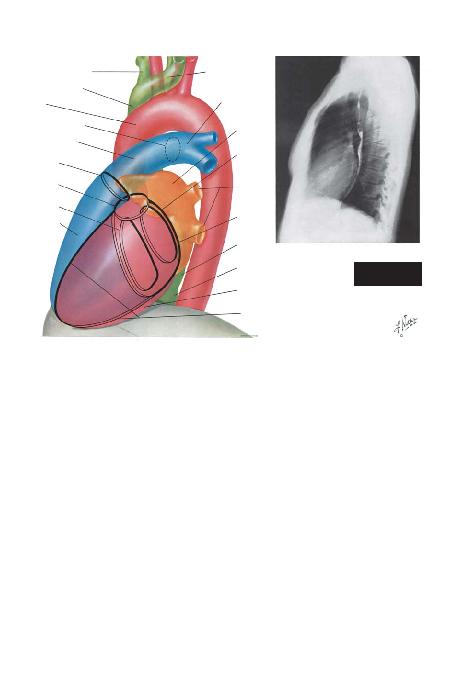

Sa¤ Anterior Oblik Görüntü (Sayfa 23). Bu gö-

rüntü temel olarak sol atriyal büyümelerinin ve sa¤

ventrikülün ç>k>fl k>sm>ndaki anormalliklerin de¤erlen-

dirilmesi amac>yla kullan>lmaktad>r. Ayr>ca mitral ka-

paktaki olas> kalsifikasyonlar>n de¤erlendirilmesi için

kullan>labilecek en iyi görüntüdür. Selektif sol ventri-

küler angiyokardiyografi s>ras>nda mitral darl>k veya

yetersizli¤in incelenmesi için kullan>l>r, çünkü mitral

kapak te¤etsel olarak görülebilmekte ve sol atriyum ta-

mamen sol ventrikülün arkas>nda izlenebilmektedir.

Bu görüntü, bu iki bofllu¤un kesiflmedikleri tek görün-

tü tipidir.

Uygun flekilde pozisyon verilmifl sa¤ anterior-oblik

görüntüde, omurgan>n gölgesi kardiyak silüetin sa¤>n-

da kal>r ve bu iki yap>y> hava içeren ince bir dikey ak-

ci¤er band> ay>r>r. Bu görüntüde aortik kemer daha k>-

sa görülür ve desandan aorta parsiyel olarak omurga ile

çak>fl>r.

Kalbin sa¤ s>n>r> yukar>da sol atriyumun posterior

k>sm>, afla¤>da ise sa¤ atriyumun posterior s>n>r> taraf>n-

dan oluflturulur. Görüntünün e¤imi artt>kça, sol atriyu-

mun profile giren k>sm> da artmaktad>r. Baryumla dolu

ösefagus kalbin bu s>n>r> ile temas halindedir ve sol at-

riyumun büyümesi ile yeri de¤iflen ösefagus en iyi bu

görüntüde görülebilir.

Kardiyovasküler silüetin sol s>n>r>n>n en üst k>sm>

neredeyse vertikaldir ve asendan aortay> temsil eder.

Bu segmentin hemen alt>nda kardiyak kontur afla¤> ve

sola do¤ru keskin olmayan bir e¤imle iner ve bu bölüm

sa¤ ventrikülün d>fla ak>m yola¤> ve pulmoner trunk ta-

raf>ndan oluflturulmufltur. Bu e¤imin inferior olarak de-

vam> sol ventrikülün anterior duvar> taraf>ndan olufltu-

rulmufltur. Frontal görüntülerde oldu¤u gibi, bu görün-

tülerde de sa¤ ventrikülün gövdesi diyafram ile temas

halindedir ve görülemez.

Mitral kapak neredeyse te¤etsel olarak saptan>r ve

kardiyak silüetin orta kesiminde görülebilir. Birbirinin

üstüne binen, kafa kar>flt>r>c> gölgelerin yoklu¤u ve

mitral kapa¤>n hareket yönünün x->fl>n>na dikey olmas>

sebebi ile bu kapakta ortaya ç>kan kalsifikasyonlar, flu-

oroskopik olarak en iyi flekilde sa¤ anterior-oblik pro-

jeksiyonda tespit edilir. Kapa¤>n eliptik yörüngesi te-

mel olarak yatayd>r. Aort kapa¤>n>n omurga ile iliflkisi

yoktur ve her ne kadar mitral kapa¤>n üst s>n>r> ile te-

mas halinde olsa da, aort kapa¤>ndaki kalsifikasyonlar,

kapak, büyük ölçüde afla¤> ve yukar> hareket ederken

belirlenebilmektedir. Bu projeksiyon ayr>ca aort ve

pulmoner kapaklar>n birbirinden ay>rt edilmesi için en

iyi imkanlar> sunar. Pulmoner kapak aort kapa¤>ndan

daha yüksek bir seviyede ve kardiyak silüetin sol s>n>r>-

na dokunacak flekilde daha soldad>r. Pulmoner kapa-

¤>n hareket çizgisi yukar> ve sa¤ do¤rudur. Trikuspid

kapak hemen hemen te¤etsel olarak ve mitral kapa¤>n

hafifçe arkas>nda görülür. Kardiyak at>m ile beraber ya-

tay olarak hareket eder ve kapa¤>n kalsifiye oldu¤u na-

dir durumlarda kolayl>kla kalsifiye bir mitral kapak ile

karfl>t>r>labilir.

Sol ventrikülün anterior k>sm>ndaki anevrizmalar

en iyi bu görüntüde tan>n>r.